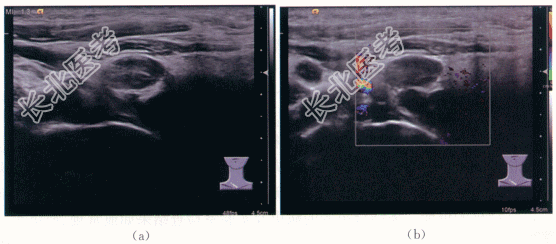

1.影像资料

双侧颈部Ⅲ区、Ⅳ区淋巴结结核,伴大片凝固性坏死,抗酸染色阳性。